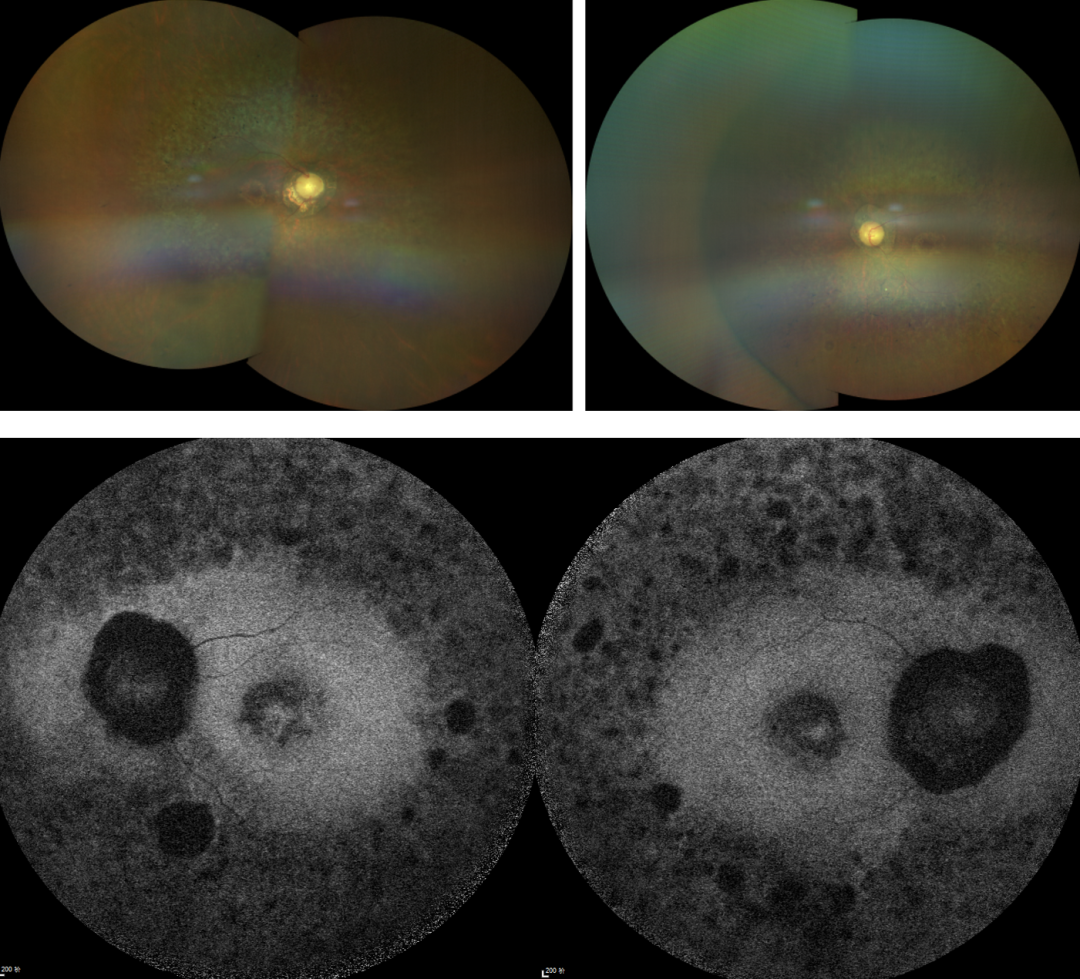

RP的診斷主要依靠眼底檢查、視野檢查、視網(wǎng)膜電圖(ERG)和基因檢測。眼底檢查可見(jiàn)典型的"骨細胞樣"色素沉著(zhù),ERG顯示視網(wǎng)膜功能下降,基因檢測可確定具體的突變基因。

視網(wǎng)膜色素變性